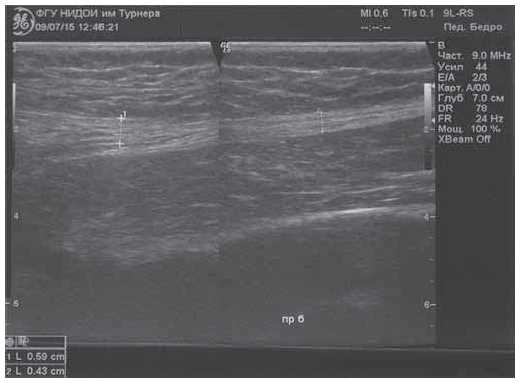

Ultrasound examination (US) of the hip joints were performed using GE LoGIQ-7 apparatus and showed a hyperechoic cord with a thickness in the upper third of the thigh of 5.9 mm, and in the middle third of the thigh of 4.3 mm, located along the lateral surface of the right thigh in the structure of the muscular tissue (Fig. 3).

Fig. 3. Fibrous cord in the soft tissues of the right thigh